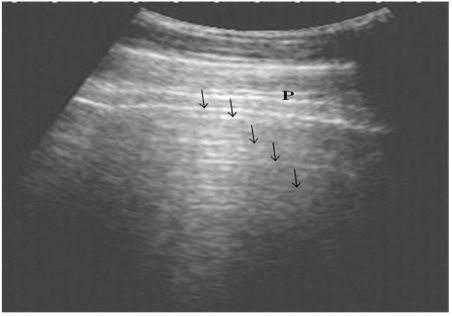

Ultrasonography of the normal lung in healthy cows using a 3.5 MHz transducer. The pleural layers appear as white linear echogenic lines. Reverberation artifacts appear as echogenic lines parallel to the pulmonary surface (Arrows). P is the parietal and visceral pleura.